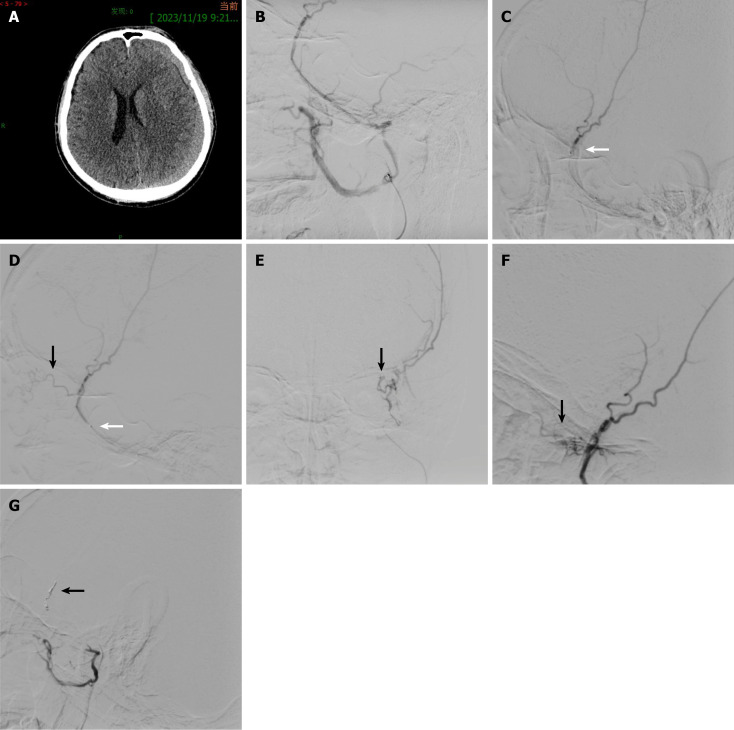

Case summary: A 60-year-old male patient presented with a headache following head trauma, and cranial computed tomography revealed a left-sided CSDH. The patient underwent left MMAE; however, polyvinyl alcohol particles inadvertently flowed into the lacrimal artery through an anastomotic artery, resulting in diplopia due to impaired abduction of the left eye. The diplopia resolved by postoperative day 40. The patient's headache resolved by postoperative day 7, and the hematoma completely resolved by postoperative day 108.

Conclusion: Potential anastomotic arteries in the middle meningeal artery (MMA) can lead to serious complications. Superselective angiography of the MMA or its branches prior to embolization is essential. Performing embolization distal to potential anastomotic sites can reduce risks, and the presence of an anastomosis may warrant coil embolization or termination of the procedure.